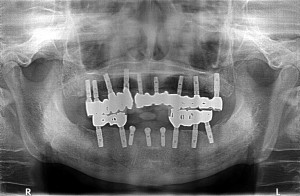

ソケットリフトを併用してオスフェリオンを填入後、

日本製マイティスアローインプラントB4008sfを埋入させて頂きました。

5ヵ月、または6ヵ月後に最終補綴物を装着させて頂く予定で終了致しました。